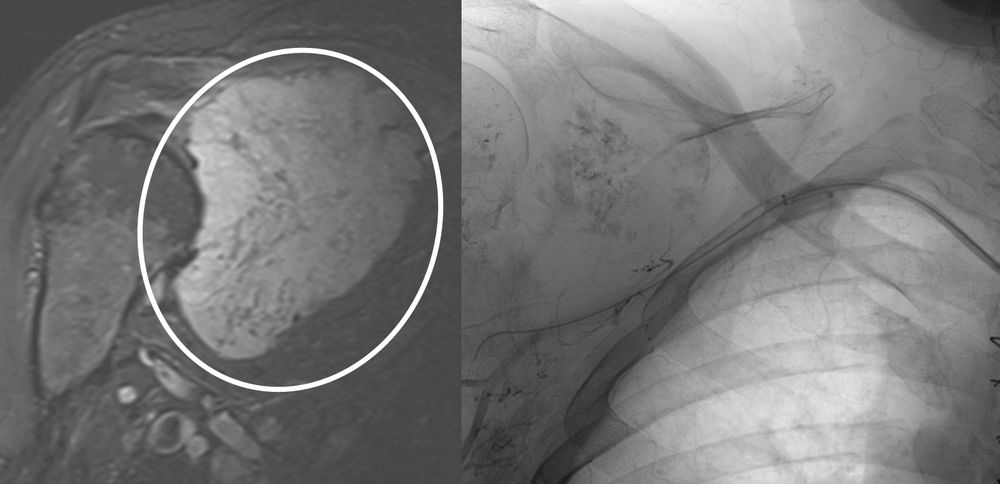

♦ Όγκους

Είτε προεγχειρητικά για την ελάττωση της αιμάτωσης του όγκου, είτε θεραπευτικά σε ορισμένες περιπτώσεις που δεν απαιτείται χειρουργείο ή υπάρχει αντενδειξη για χειρουργική αφαίρεση του όγκου.

Συνοπτικά υπό την καθοδήγηση του αγγειογράφου, αναγνωρίζεταιτο παθολογικό αγγείο-αγγεία και με ειδικούς καθετήρες και μικροκαθετήρες, διοχετεύονται εμβολικά υλικάόπως μικροσφαιρίδια ή coils, ώστε να αποφραχθεί ή να μειωθεί η παθολογική αγγείωση.